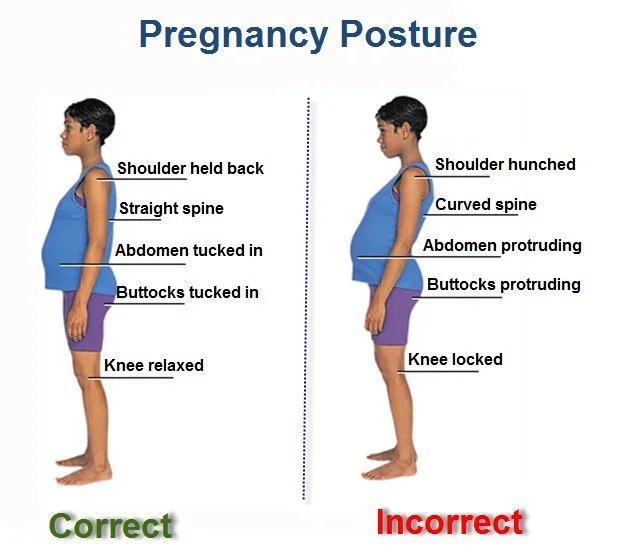

There are a number of body changes that mothers experience during and after their pregnancies that can cause unique challenges and that often get overlooked in prenatal and post-partum care. These challenges involve increasingly new spine stresses, adaptations, and difficulties maintaining a “neutral spine”.

A neutral spine is the ability to maintain the natural curves of the spine that allow for shock absorption when we stand and walk and allow for our center of mass to be maintained at our belly button region. Women are often challenged through their pregnancies to maintain neutral spine postures due to the fast changing size of the babies and the increased distribution of weight in their mid section.

As a way to compensate and maintain balance, women often lock their knees and excessively lean their top half backwards in order to counterbalance the forward pull of the baby’s weight. For some women these postural asymmetries correct after the baby is delivered and their weight distribution normalizes. However, for many women, due to abdominal weakness and having altered postures for many months through their pregnancy, they have a hard time normalizing their posture. These changes, over time can contribute to low back and hip pain.